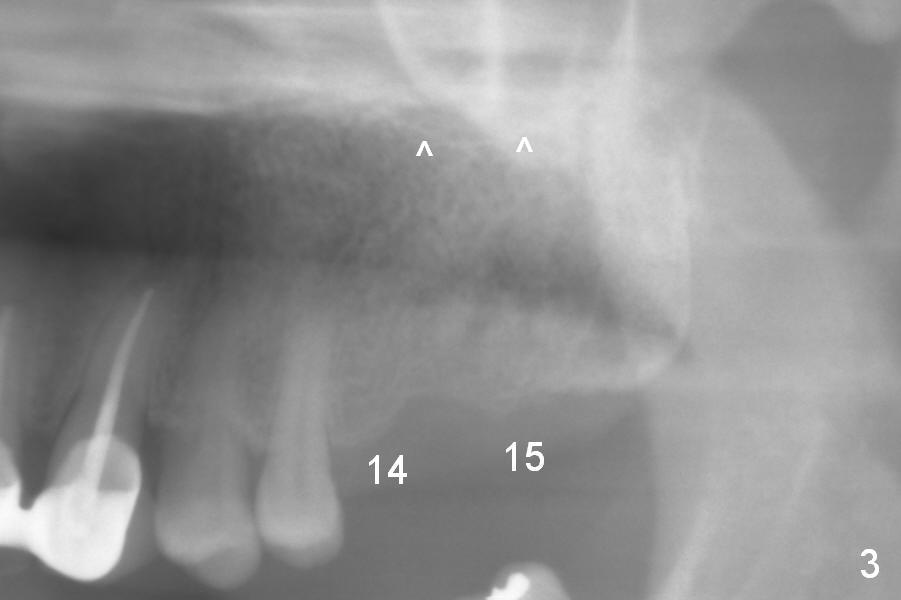

A 52-year-old man has multiple missing teeth. Since he has a lower partial denture (Fig.5), implants will be placed at the sites of #14 and 15 first (Fig.1). The site of #14 may need bone expansion if bone density is low, whereas the ridge at #15 is wide (Fig.2). There is no problem in height at the sites of #14 and 15 (Fig.3).

The buccolingual width at the sites of #19 and 21 appears narrow (Fig.4). On the other hand, the mesiodistal width at #19 seems to be wider than one molar and narrower than two (Fig.4-6). If CBCT and/or surgery confirms that the buccolingual bony width is narrow, two small diameter implants will be placed with restoration of two bicuspids.

CBCT confirms that the ridge at #14 is narrower than that at #15. In contrast, the bone density is lower at #15 than that at #14 (Fig.7-9). If the keratinized tissue is wide, use 4 mm tissue punch (3 mm from #13). If incision is made, wheel saws will be used to split the ridge. Or use Magic split and osteotomes. Bone expanders are going to be used for bone expansion at #14 and bone condensation at #15 (Fig.8,9). Be careful while using bone expanders at #14, since the bone density is higher. There is a chance of plate fracture. Use drills if indicated. Fabricate splinted provisional after placement of abutments.